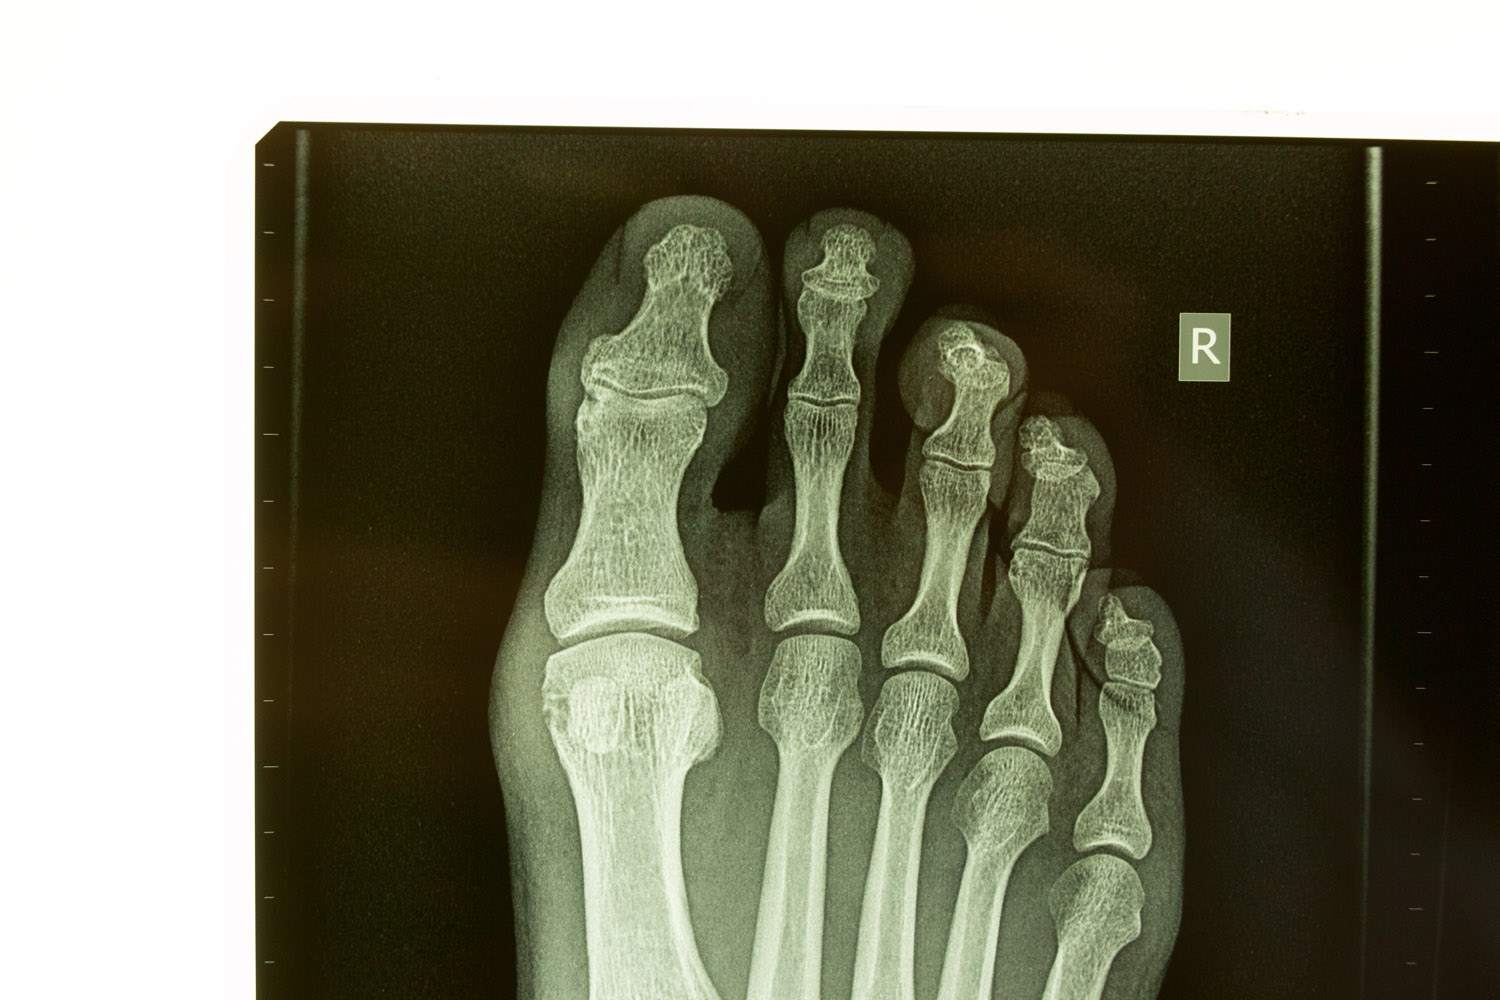

irrefutable evidence June 13, 2014injuryfucked, x-raystriker Almost a year later the foot is still sore, X-rays show “…early osteoarthritis involving the distal interphalangeal joint of the big toe and a fracture near the head of the proximal phalanx…”. Awesome.